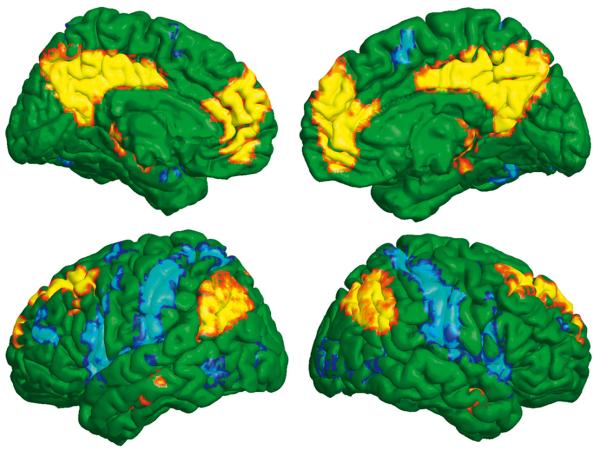

Minione dwie dekady to nieustający postęp w podglądaniu na żywo pracy mózgu. Czy przybliżyły nas one do odpowiedzi na kluczowe pytanie: jak ten organ naprawdę funkcjonuje?

Czy mózg myśli cały, czy do poszczególnych zadań, np. rozpoznawania twarzy lub liter, wykorzystuje wyspecjalizowane rejony?